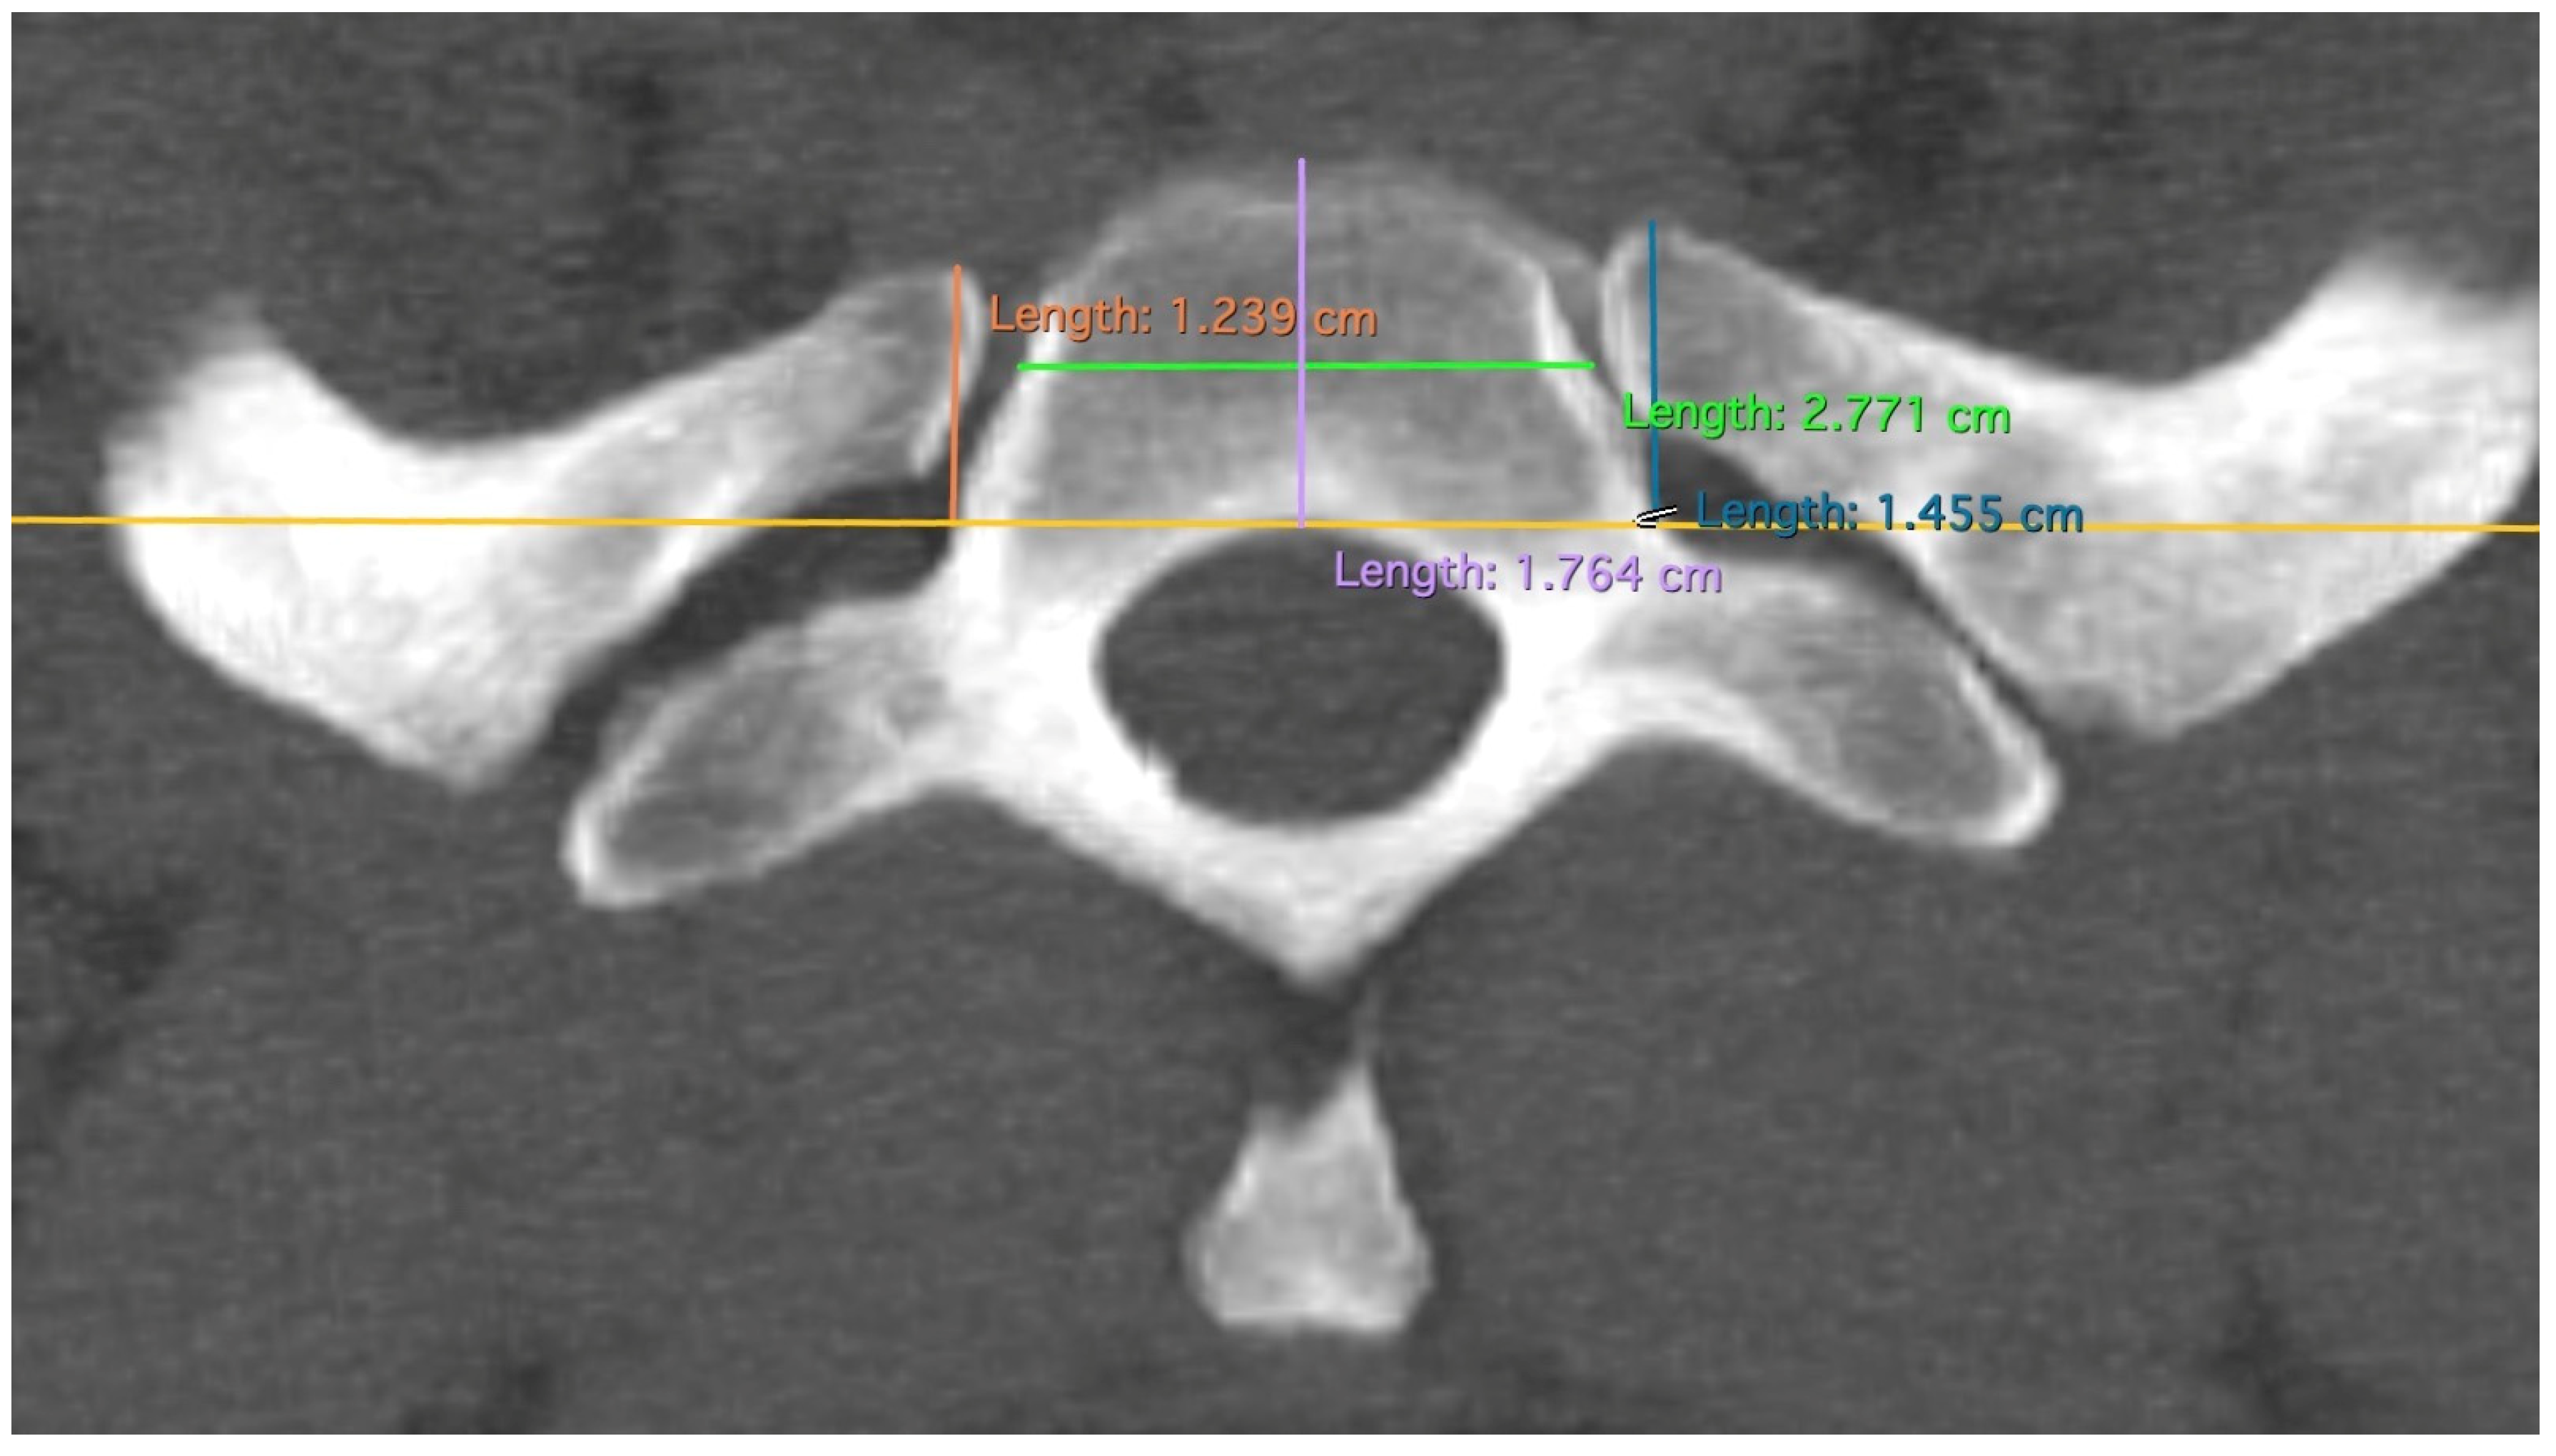

Figure 4.

Measurement of RAP, VBW, and VBD; measurements of RAP as a perpendicular line to the tangent (yellow line) of the posterior edge of the first thoracic vertebral body. Differently colored lines for better differentiation.

The depth and width of the first vertebral body were measured and statistically tested in the same way as the other measurements (Figure 4). The data from these two measurements were discarded in the interpretation because no conclusions could be drawn from them. Measurements were taken using Horos software (version 3.3.6). After multiplanar reformation (MPR) of the CT data, the rib could be displayed in sagittal, frontal, and horizontal planes and was now positioned and measured in a standardized manner.